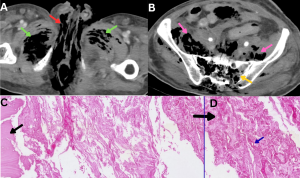

Fig 25: Clinical history:

A 38-year-old immunocompromised patient presented with abdominal pain and vomiting.

Figures A–C:

Axial, coronal, and sagittal contrast-enhanced CT (CECT) abdomen images demonstrate marked circumferential wall thickening of the jejunal and ileal loops (yellow arrows), consistent with small-bowel involvement.

Figure D:

Histopathology demonstrates necrotic small-bowel wall with muscle fibers (black arrows) infiltrated by broad, pauciseptate fungal hyphae (blue arrow), confirming mucormycosis.